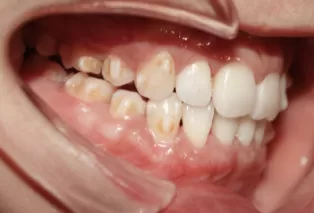

Photos intra-orales